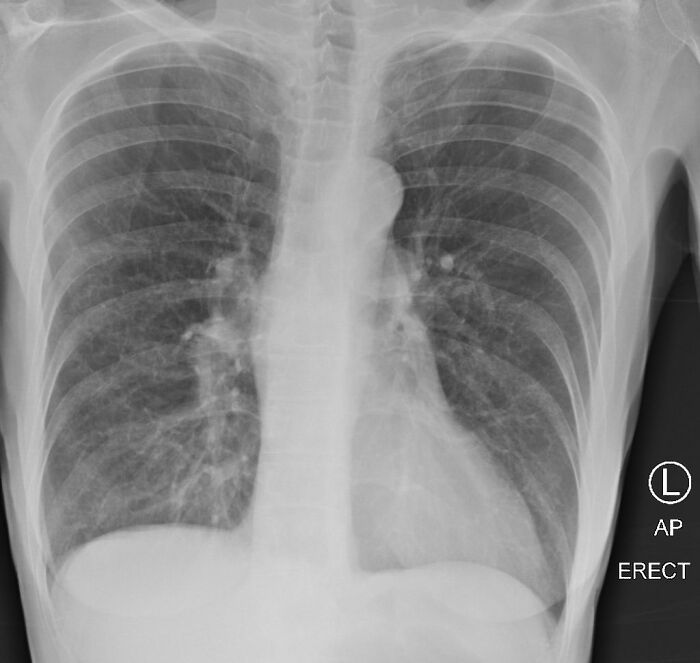

La tercera imagen muestra pulmones post-COVID que parecen estar casi completamente blancos, lo que significa que los pulmones están severamente dañados

Después de que su tweet ganara mucha atención y recibiera miles de respuestas, se invitó a la Dra. a decir algunas palabras durante las noticias en la CBS DFW. «Todo el mundo está tan preocupado por la cuestión de la mortalidad y eso es terrible y horroroso», señaló la Dra. Brittany Bankhead-Kendall. «Pero hombre, y todos los supervivientes y las personas que han dado positivo, esto es, va a ser un problema».

Como se puede deducir de la comparación de rayos X, los pulmones post-COVID se ven mucho peor que los de un fumador

«Todavía hay personas que dicen ‘Estoy bien, no tengo ningún problema’, y cuando les haces una radiografía de tórax se obtiene una radiografía muy mala», dijo la Dra. a CBS DFW. «O verás muchas de esas cicatrices blancas y densas o las verás en todo el pulmón. Y si no sientes problemas ahora, el hecho de que esté en la radiografía de tu tórax, es un indicativo seguro de que usted posiblemente tendrá problemas más adelante».

Aparentemente, incluso los pacientes asintomáticos muestran una radiografía de tórax grave entre el 70 y el 80 por ciento de las veces. El Dr. Bankhead Kendall también agrega que si un paciente post-COVID tiene dificultad para respirar, debe mantenerse en contacto con su médico de atención primaria.